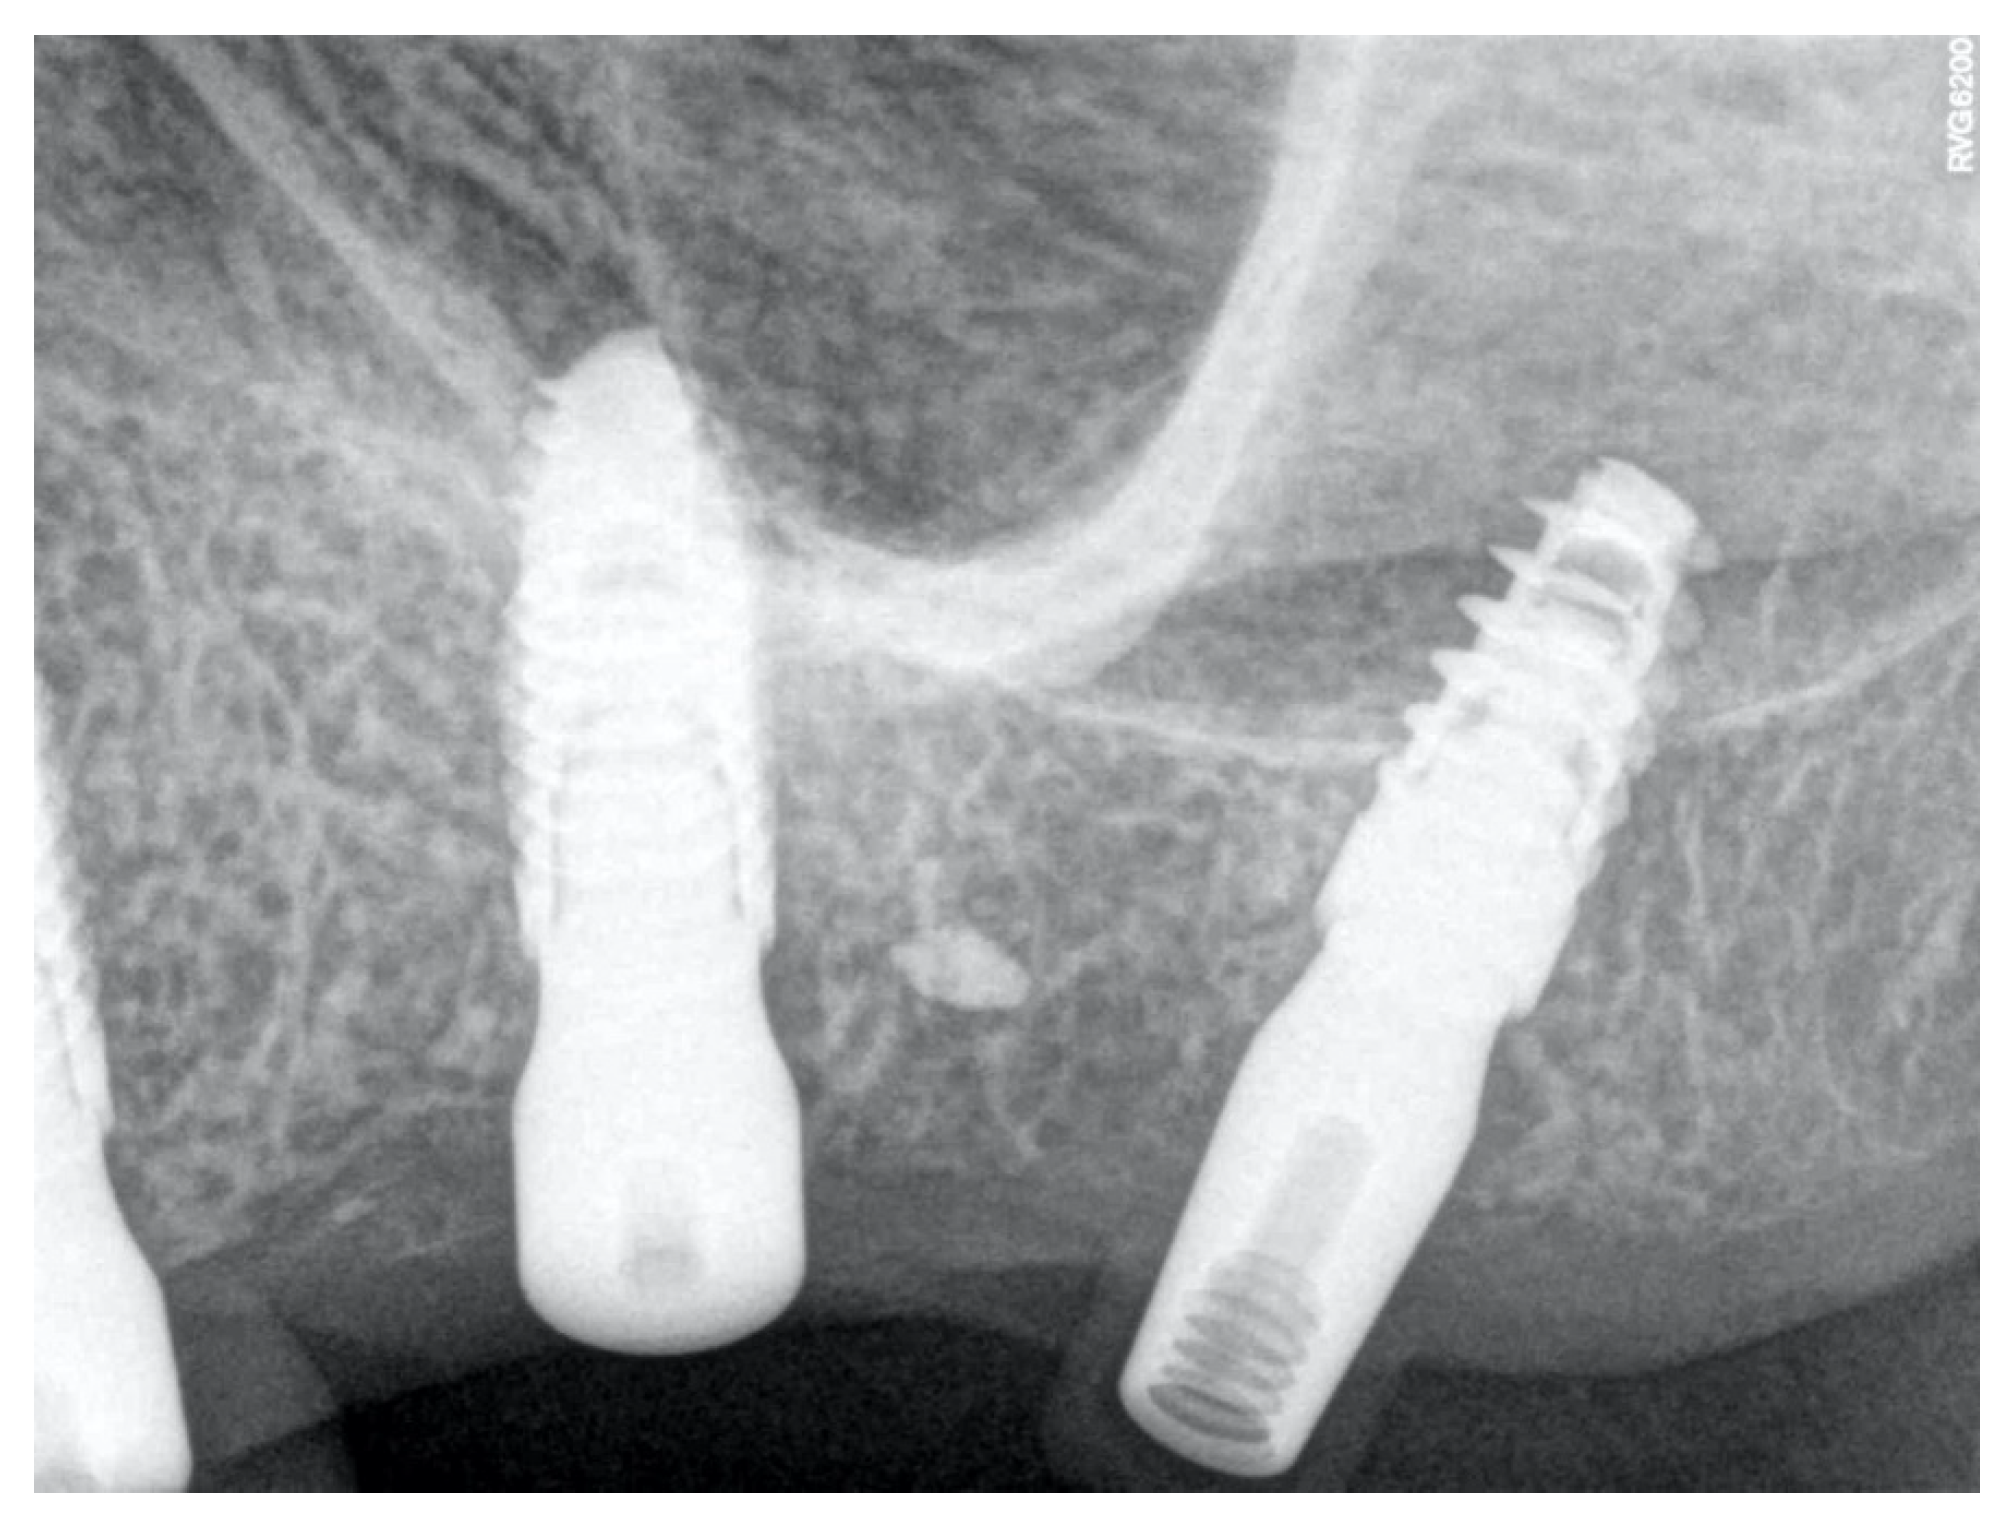

Case Report of a Dental Implant with Conometric Abutment–Prosthetic Cap Connection: Advanced High-Resolution Imaging and Peri-Implant Connective Tissue Performance

2. Materials and Methods

2.1. Samples